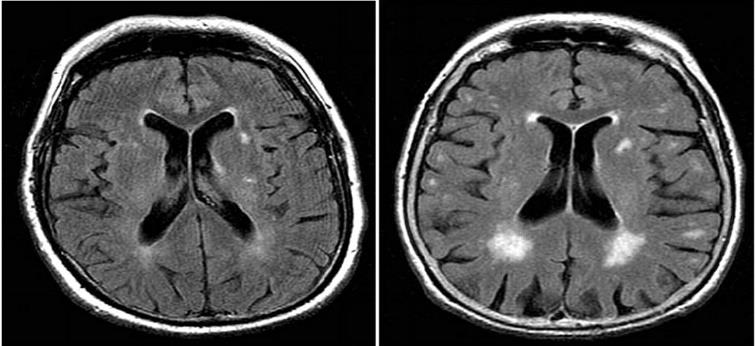

Figure 1:MRI Findings T2/ Flair-periventricular hyperintensities

unremarkable for cerebello-pontine T2 hyperintensities. (likely due to the

disease’s rapid progression)

Brain MRI demonstrated periventricular T2/FLAIR hyperintensities. The pathognomonic ‘hot cross bun’ sign of pontine degeneration was absent; however, absence of this finding does not exclude MSA, particularly in early stages. [1,9] Blood investigations including complete blood count, metabolic panel, thyroid function, serum B12, VDRL, and HIV serology were within normal limits, excluding common metabolic and infective causes of psychosis. An electroencephalogram showed no epileptiform activity.